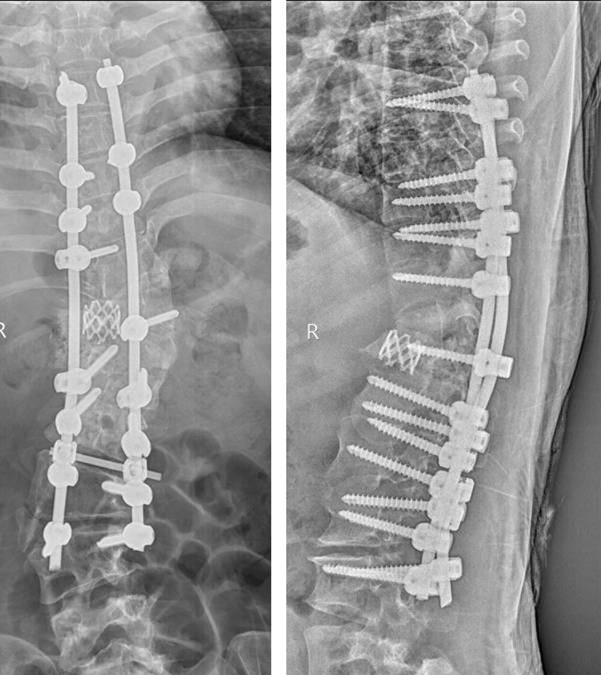

术后外观照及X线正侧位

来自我省咸阳市的患者张某,因胸腰部脊柱畸形30余年,腰部疼痛1月慕名来我院求诊。患者为成年女性,诊断为先天性脊柱侧弯。病程长,儿时有过手术史,侧弯Cobb角度超过90度。入院后科内反复讨论,研读患者的影像学资料,并采用3D打印重现患者脊柱骨性结构(1:1)。在此基础上,制定了详细的术前计划及整体治疗方案。治疗过程中,采取骨性牵引2周,缓解手术矫形时神经肌肉血管的张力,降低手术风险,手术当天,由贺西京教授主刀,李浩鹏教授,王栋副教授,赵波、秦杰主治医师、王放住院总医师密切配合,在麻醉科及手术室的协助下,施行截骨矫形手术。术中诱发电位监护、自体血回输,唤醒试验、中心静脉压、外周动脉压监护、保温毯等措施保护患者的生命安全及神经功能。患者畸形严重,手术非常复杂,稍有不慎即有可能导致瘫痪,给患者和家属带来严重负担。贺西京教授、李浩鹏教授、王栋副教授等手术麻醉人员全神贯注,一丝不苟,连续手术8小时,患者脊柱畸形明显纠正,侧凸Cobb角纠正至20°,生命体征及神经功能完好,患者截骨矫形手术顺利完成。术后在我科护理和我院康复科医师的精心护理康复下,患者1周下地站立行走,顺利康复。术后无明显并发症,患者及家属对手术效果非常满意,现已出院。